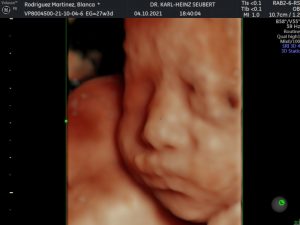

- Ultrasonido 2D, 3D, 4D incluidos

- Cuento con ultrasonido de ultima generación Voluson P8. con alta resolución, ultrasonido 4D incluido sin costo extra. Ultrasonido 4D

ULTRASONIDO 4D INCLUIDO